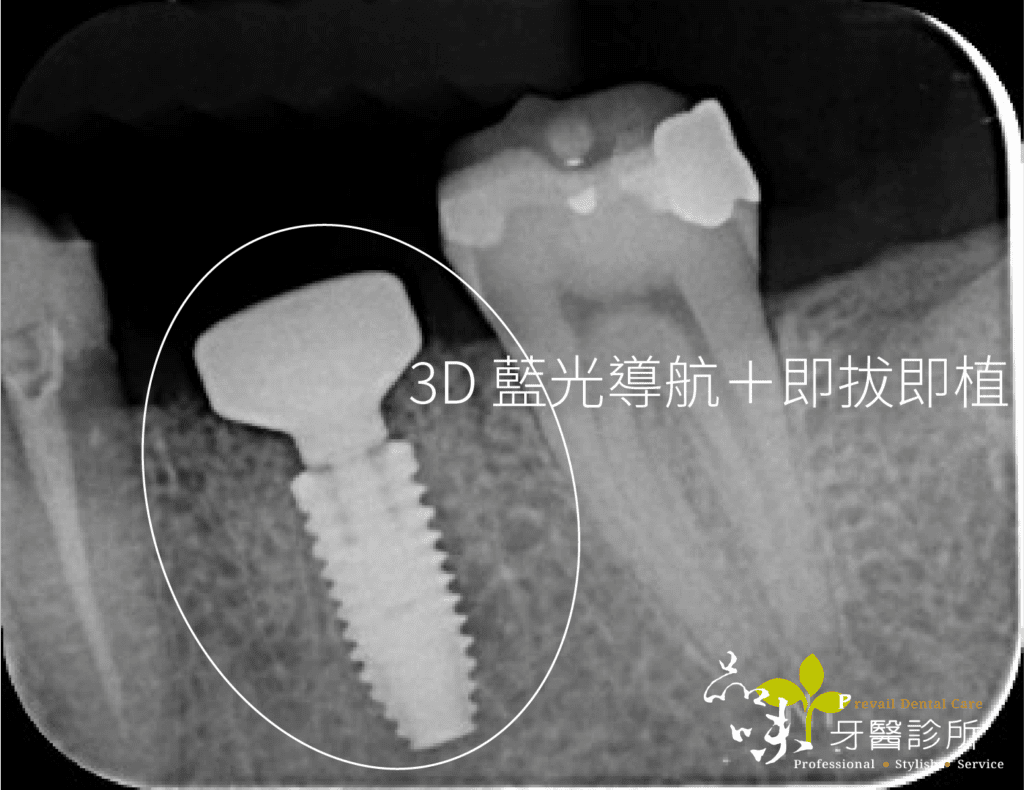

由於即拔即植是屬於精準度要求較高的手術,若醫療院所提供導引式植牙或 3D 藍光導航植牙等設備,能夠增加定位的精準度。筆者服務的診所兩種植牙設備均有引進,可以照患者不同的條件做選擇。

文首提到牙裂的陳先生,當天下午就安排了手術。在一系列數位資料蒐集後,進行藍光導航植牙。傍晚陳先生的牙齒就不疼了。

傷口在幾天後再也沒有疼痛感,後續回診追蹤也沒有不舒服。就這樣,四個月很快地過去了,假牙醫師幫他裝好全陶瓷的假牙。現在他可以開開心心地盡情享用美食。